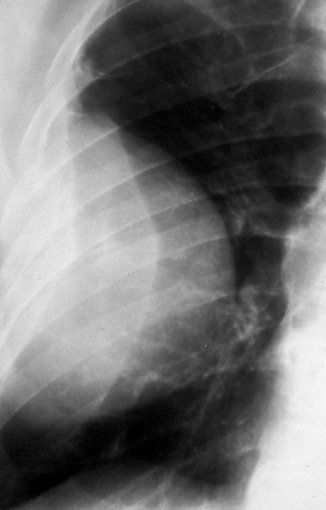

Fig. 13a: Posterior-anterior chest radiograph shows a large peripheral cancer in the right lung with rib destruction, T3.